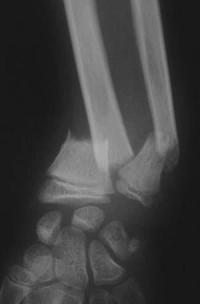

Fracture métaphysaire du poignet